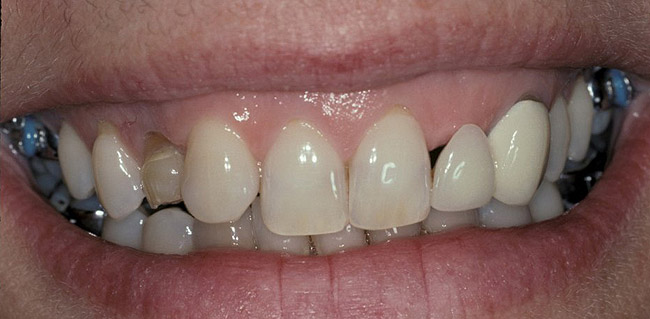

Figure 6  Initial view of this patient depicts the esthetic disharmony and smile imbalance. There was a retained primary maxillary canine on the right, a permanent canine in place of the right lateral incisor, a missing tooth No. 10 replaced with a cantilever restoration, asymmetric gingival margins, recession on tooth No. 11, and uneven incisal edges.

Figure 6

Figure 7   Completion of maxillary orthodontic treatment created adequate space for implants at site Nos. 7 and 10. The retained right primary maxillary canine was extracted and orthodontic movement was performed to translate the right permanent canine into the No. 6 position, creating room for a No. 7 implant, and generally align the teeth.

Figure 7